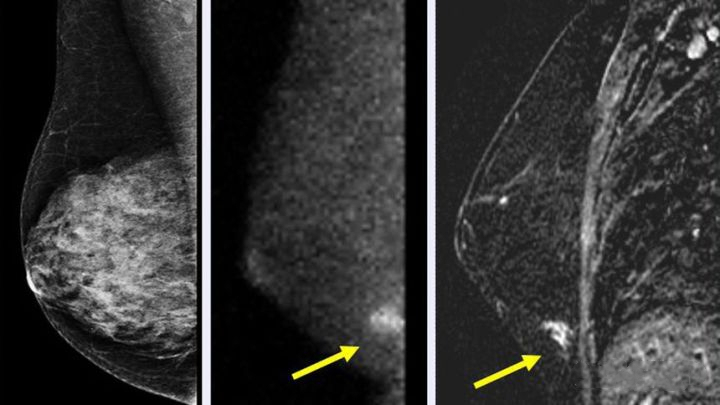

1. 乳腺X线(钼靶)检查:该检查简便易行,对降低40岁以上妇女乳腺癌死亡率效果明显。但乳腺X线对年轻致密乳腺组织穿透力差,故一般不建议对40岁以下、无明确乳腺癌高危因素或临床体检未发现异常的妇女进行乳腺X线检查。常规乳腺X线检查的射线剂量低,不会危害妇女健康,但正常女性无需短期内反复进行乳腺X线检查。

而且这个检查不用担心“飞机场”没法拍摄钼靶,放射科医生会想办法让无论是半球形还是锥形的乳房在检查仪器上就位的。以下显影结果都是乳腺癌患者癌肿的影像。

图片来源网络,侵删!